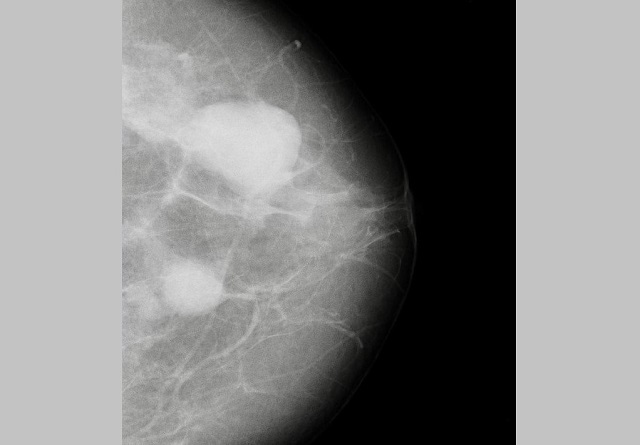

В Набережных Челнах у пациентки обнаружили два объемных образования молочной железы во время промышленной диспансеризации.

Женщине чуть больше 40 лет. Она пришла на диспансеризацию в поликлинику по направлению от работодателя. На маммографии врачи обнаружили образования. Сейчас пациентка наблюдается у врача-онколога.

Медики отмечают, что многие болезни на ранних стадиях могут себя не проявлять. Диспансеризация поможет их диагностировать.

Фото: телеграм-канал «Горздрав Челны»